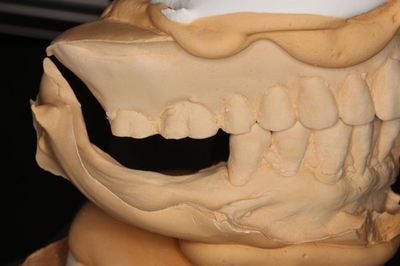

模型でシミュレーションするために事前に型取りと

フェイスボウトランスファーを行います。

模型上でイメージを作ります。